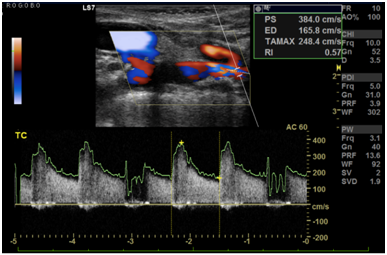

Cranioencephalic computerized tomography excluded acute ischemic lesions.CDS revealed severe stenosis of the innominate artery (PS 38 cm/s) (Figure 1), occlusion of right vertebral artery, total flow inversion of the right internal carotid artery (ICA) (Figure 2), partial endosystolic flow inversion of right CCA (Figure 3) and low amplitude anterograde flow of right external carotid artery, no significant lesions were found on the left carotid axis. Computerized tomography angiography (CTA) excluded significant carotid lesions and revealed pre-occlusive stenosis of the innominate artery by a calcic lesion (Figure 4).Surgical approach consisted of ultrasound-guided puncture of right brachial artery and surgical exposure of right CCA. Brain protection was achieved by direct clamping of the common carotid artery and subsequently carotid and axillary retrograde endovascular access was obtained. Placement of 6F introducer on brachial artery and 8F on right CCA (Figure 5). After pre-dilatation with a 4x40mm balloon (Admiral Xtreme™, Medtronic), a kissing stent technique was performed with a 6x59mm covered stent (AdvantaV12™, Getinge) on the right CCA and 7x57mm balloon-expandable stent (Visi-Pro™, Medtronic) on the right subclavian artery. At the end of the procedure direct expulsion of eventual embolic material was performed prior to declamping and a good permeability of the revascularized arteries was verified (Figure 6). Clamping time was under 1minute. The postoperative period was uneventful and patient was discharged 3days later.

Figure 2 Right internal carotid artery with total flow inversion.

Figure 3 Partial endosystolic flow inversion of right common carotid artery.